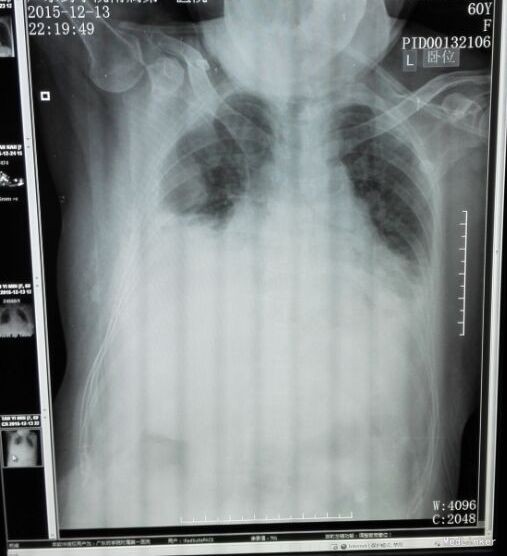

患者入院后予“美洛西林舒巴坦”抗感染,当天晚上出现明显气促,伴右后下背痛,无明显发热,当时复查胸片示: 1、双下肺炎症、双侧胸腔积液,同2015.12.13前片比较,考虑右侧胸腔积液明显增多,部分包裹,建议CT进一步检查。血气分析未见明显异常,2015-12-14 复查急诊血常规:白细胞计数 24.290(10E9/L)↑,淋巴细胞计数 0.750(10E9/L)↓,中性粒细胞比例 0.930↑,血红蛋白浓度 104.000(g/L)↓,中性粒细胞计数 22.590(10E9/L)↑,红细胞计数 3.500(10E12/L)↓,血小板计数 466.000(10E9/L)↑,单核细胞计数 0.920(10E9/L)↑;急诊肾功(三项):尿素氮 8.450(mmol/L)↑;急诊电解质(K/Na/Cl):钠 128.700(mmol/L)↓,氯 87.100(mmol/L)↓; 2015-12-14胸部及上腹部CT平扫+增强示:1、两中下肺多发炎症,部分萎陷。建议治疗后复查。2、双侧胸腔积液(右著);心包少量积液。3、结合病史,右输尿管术改变;右侧双J管置入术后。右肾、输尿管上段扩张、积水,右肾周感染并少许积气;左肾结石。4、脂肪肝。5、胆、脾、胰未见异常。因CT提示肺部大片实变,包裹性积液(量少),考虑重症肺炎可能,于2015-12-14将抗生素升级为“亚胺培南西司他丁 1.0 q8h、万古霉素 50万U q12h、伏立康唑 0.2 q12h”三联,同时予“甲强龙”抗炎等治疗。经治疗,患者气促症状逐渐缓解,咳嗽、咳痰、右后背疼痛好转,无发热,精神、胃纳较前改善。因B超定位下胸水量少,暂未予胸穿。2015-12-17复查胸部+上腹部CT平扫示:1、双中下肺炎炎症较前吸收好转,右侧胸腔积液较前略有减少,左侧胸腔积液现已基本吸收。2、胸、腹主动脉粥样硬化;心包少量积液(大致同前)。纵膈内临界肿大淋巴结。3、右输尿管术改变;右肾、输尿管上段扩张、积水,右肾周慢性感染(原右肾周积气消失);左肾结石。4、轻度脂肪肝。少量腹水。5、胆囊内斑片状高密度影,考虑胆汁淤积。2015-12-19 复查血常规:白细胞计数 18.160(10E9/L)↑,中性粒细胞比例 0.918↑,血红蛋白浓度 105.000(g/L)↓,中性粒细胞计数 16.670(10E9/L)↑,红细胞计数 3.560(10E12/L)↓,血小板计数 396.000(10E9/L)↑,淋巴细胞比例 0.037↓,红细胞压积 0.305↓,单核细胞计数 0.780(10E9/L)↑;降钙素原 2.000(ng/ml)↑;急诊肾功(三项):肌酐 146.000(umol/L)↑,尿素氮 19.580(mmol/L)↑。2015-12-20患者精神较前明显变差,伴纳差、乏力,气促较前加重,2015-12-20再次复查血常规:白细胞计数 33.230(10E9/L)↑,中性粒细胞比例 0.967↑,红细胞计数 3.350(10E12/L)↓,中性粒细胞计数 32.130(10E9/L)↑,血红蛋白浓度 99.000(g/L)↓,单核细胞比例 0.016↓,淋巴细胞比例 0.016↓,红细胞压积 0.293↓;2015-12-20 急诊肾功(三项):肌酐 125.000(umol/L)↑,尿素氮 15.960(mmol/L)↑;降钙素原 0.836(ng/ml)↑;复查胸片示:1、同2015.12.17胸部CT比较,考虑右侧胸腔积液较前有所增多,大部分为包裹性积液,新发左侧胸腔少量积液;右肺情况显示不清,左下肺炎症。2、心影增大,结合CT考虑心包积液;主动脉粥样硬化。遂行胸腔穿刺术,抽出400ml黄白色脓性胸水,胸水常规:PH6.0,WBC54600*10E6/l,中性粒0.97,胸水生化:乳酸脱氢酶 2221.000(U/L);葡萄糖 1.180(mmol/l),总蛋白 24.000(g/l),腺苷脱氨酶 154.000(U/L),氯 106.800(mmol/L)。符合脓胸改变,予右侧胸负压腔闭式引流,同时予“庆大霉素16万u”冲洗,将抗生素降级为莫西沙星片口服,患者症状明显好转,12.24复查胸片及CT胸腔积液及肺炎均较前明显好转。